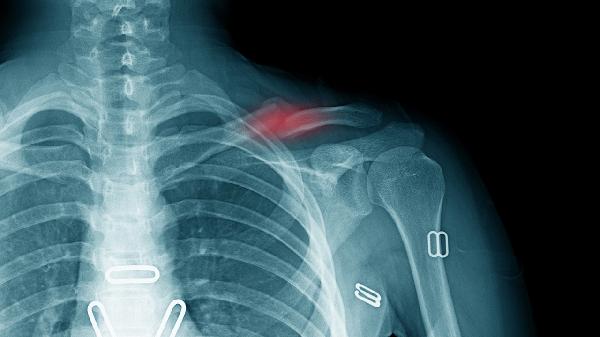

5、雷诺现象

部分患者伴随肢体远端遇冷后苍白-青紫-潮红的三相颜色变化,提示锁骨下动脉受压。严重者可出现甲床毛细血管异常,但不同于原发性雷诺病,这种继发性现象多呈单侧性发作。